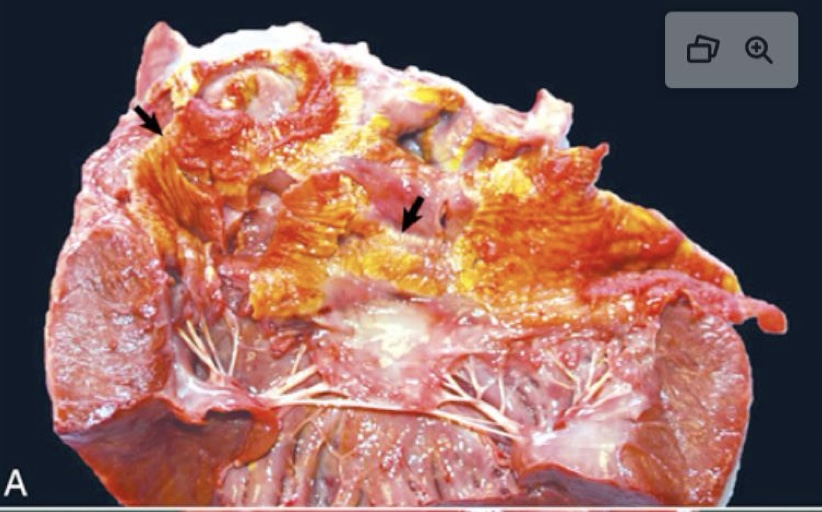

what are the arrows showing?

endocardial mineralization